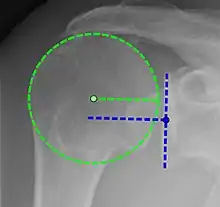

Projectional radiograph of normal glenohumeral position.[51]

High-riding humeral head in a rotator cuff tear.

X-ray projectional radiography cannot directly reveal tears of the rotator cuff, a 'soft tissue', and consequently, normal X-rays cannot exclude a damaged cuff. However, indirect evidence of pathology may be seen in instances where one or more of the tendons has undergone degenerative calcification (calcific tendinitis). The humeral head may migrate upward (high-riding humeral head) secondary to tears of the infraspinatus, or combined tears of the supraspinatus and infraspinatus.[51] The migration can be measured by the distance between:

• A line crossing the center of a line between the superior and inferior rims of the glenoid articular surface (blue in image).

• The center of a "best-fit" circle positioned over the humeral articular surface (green in image)

Normally, the former is positioned inferiorly to the latter, and a reversal therefore indicates a rotator cuff tear.[51] Prolonged contact between a high-riding humeral head and the acromion above it may lead to X-ray findings of wear on the humeral head and acromion; secondary degenerative arthritis of the glenohumeral joint (the ball and socket joint of the shoulder), called cuff arthropathy, may follow.[50] Incidental X-ray findings of bone spurs at the adjacent acromioclavicular joint may show a bone spur growing from the outer edge of the clavicle downward toward the rotator cuff. Spurs may also be seen on the underside of the acromion, once thought to cause direct fraying of the rotator cuff from contact friction, a concept currently regarded as controversial.